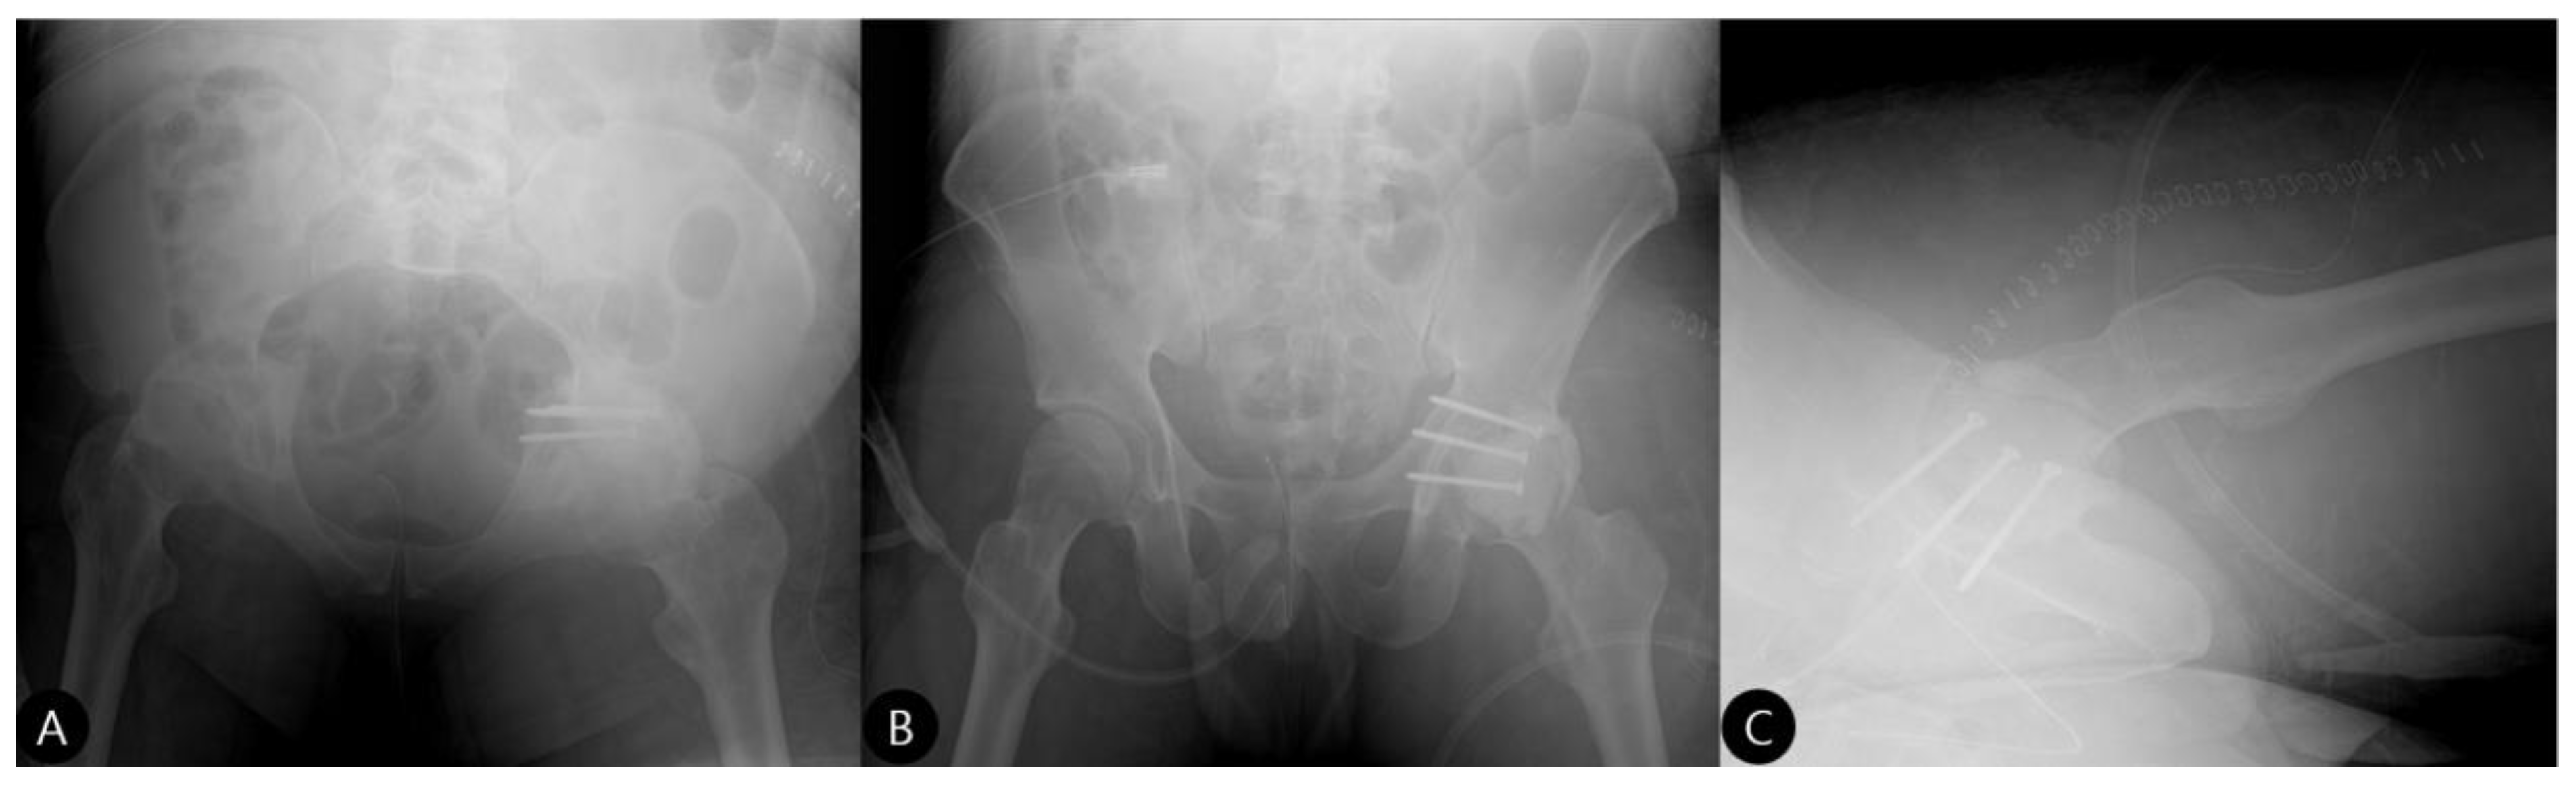

- Reduction and Final Assessment: The hip was reduced under direct vision. Intraoperative fluoroscopy confirmed a concentric reduction, correct implant placement, and the absence of cement fragments in the joint. The stability of the construct was tested through a range of motion. Postoperative imaging confirmed the anatomical reduction and the accurate contouring of the cement construct (Figure 4 and Figure 5).

- 3 Months: Radiographs showed a stable hip construct with no signs of subluxation or screw migration (Figure 7). The patient had returned to activities of daily living without major discomfort. The mHHS was 78/100.